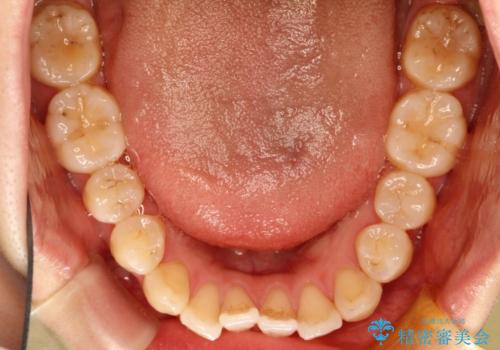

初診時の歯並びの状態としては、上下ともに前歯部に限局した軽度ののがたつき(叢生)がある状態でした。

主に歯列弓の拡大とディスキング(歯と歯の間に隙間を作る処置)を行い叢生を改善しました。